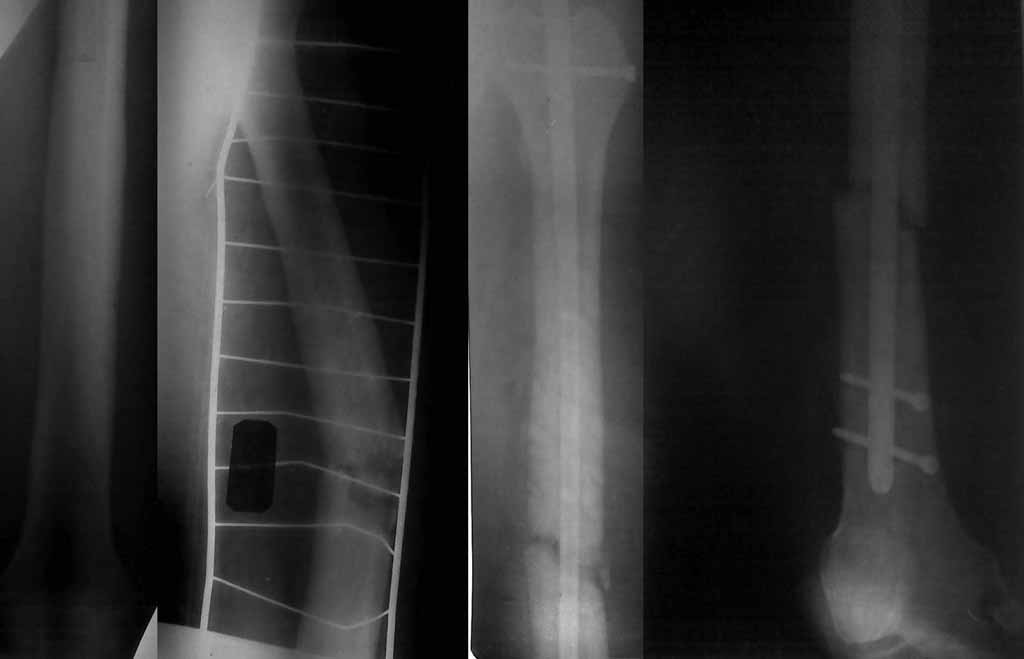

Патологический перелом бедра

Обратился в марте в связи с усилением болевого синдрома, при осмотре признаков патологии коленного сустава не обнаружили, левое бедро пастозно. при пальпации на границе с/3-н/3 бедра чёткая граница уплотнения и резкое усиление боли. Движения в суставах в норме. В анализе крови всё в норме кроме лифоциты 50%, сегментоядерные 21%. Сцинтиграфия с Тс - накопление в канале н/3 бедра и параоссально 500%. Рентгенологически - утолщение надкостницы по типу муфты.

Выполнена открытая биопсия. вокруг бедренной кости обнаружена платная ткань серо-белого цвета, толщиной до 1см, неплотно связанная с костной тканью, под такнью накостницы нет, выполнена трепанация канала, костная ткань слерозировання, в канале аналогичная ткань. Патологическая ткань удалена

Гистологически фибросаркома. Ткань исследована гистохимическим методом - Неходжкинская, В-крупноклеточная лимфома бедра. В послеоперационном периоде болевого синдрома не было (говорит стал нормально спать без обезболивающих)

26 марта при незначительной травме - поперечный перелом бедра в месте трепанации.

Выполнена закрытая репозиция БИОС с первичной динамизацией. Ходит с дозированной нагрузкой на левую ногу.

Так как это лимфома, то пациенту, можно сказать, повезло. Если бы это была фибросаркома, как предполагалось первоначально, то после БИОС, разговор бы возможно шёл об ампутации. Лимфома обычно очень хорошо реагирует на химию и лучевую терапию. Химию обычно можно начать через 2 недели после операции. Лучевую терапию начинают через 6-8 недель после операции. Все эти сроки, с условием, что рана нормально заживает. Перелом будет заживать медленнее, чем обычный, так как сама опухоль, химия и радиация замедляют образование костной мозоли. Не видя снимков затрудняюсь что либо сказать про нагрузку на конечность.

Здравствуйте, коллеги. Досылаю рентгенограммы, качество низкое, извините.